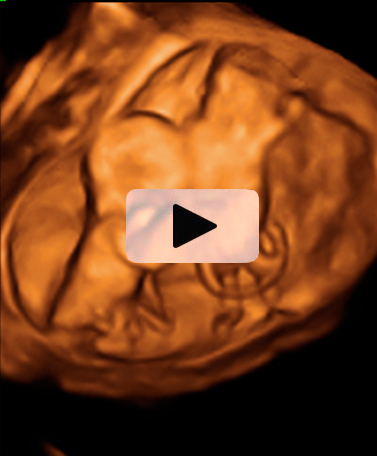

Ecografía semana 12: Gemelos en bolsas independientes

La membrana es muy gruesa

Imagen de un embarazo gemelar que recoge tres ecografías 2D y una en 3D. Los cuatro ultrasonidos demuestran que los bebés están alojados en bolsas independientes con placentas también independientes. Y la membrana que separa los fetos es muy gruesa, según se aprecia en la imagen tridimensional.